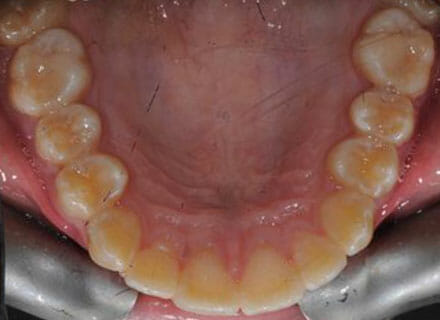

Fixing protruding teeth upper and lower and crowding – no extractions

this patient didn’t like the teeth because they pushed forwards and were sticking out and pushing out her lips. She thought that she looked like she had too many teeth and not enough space. In 12 months we pulled all the teeth back, pulled them together, and lined them all up. No teeth were extracted because we made room by expanding the jaws.